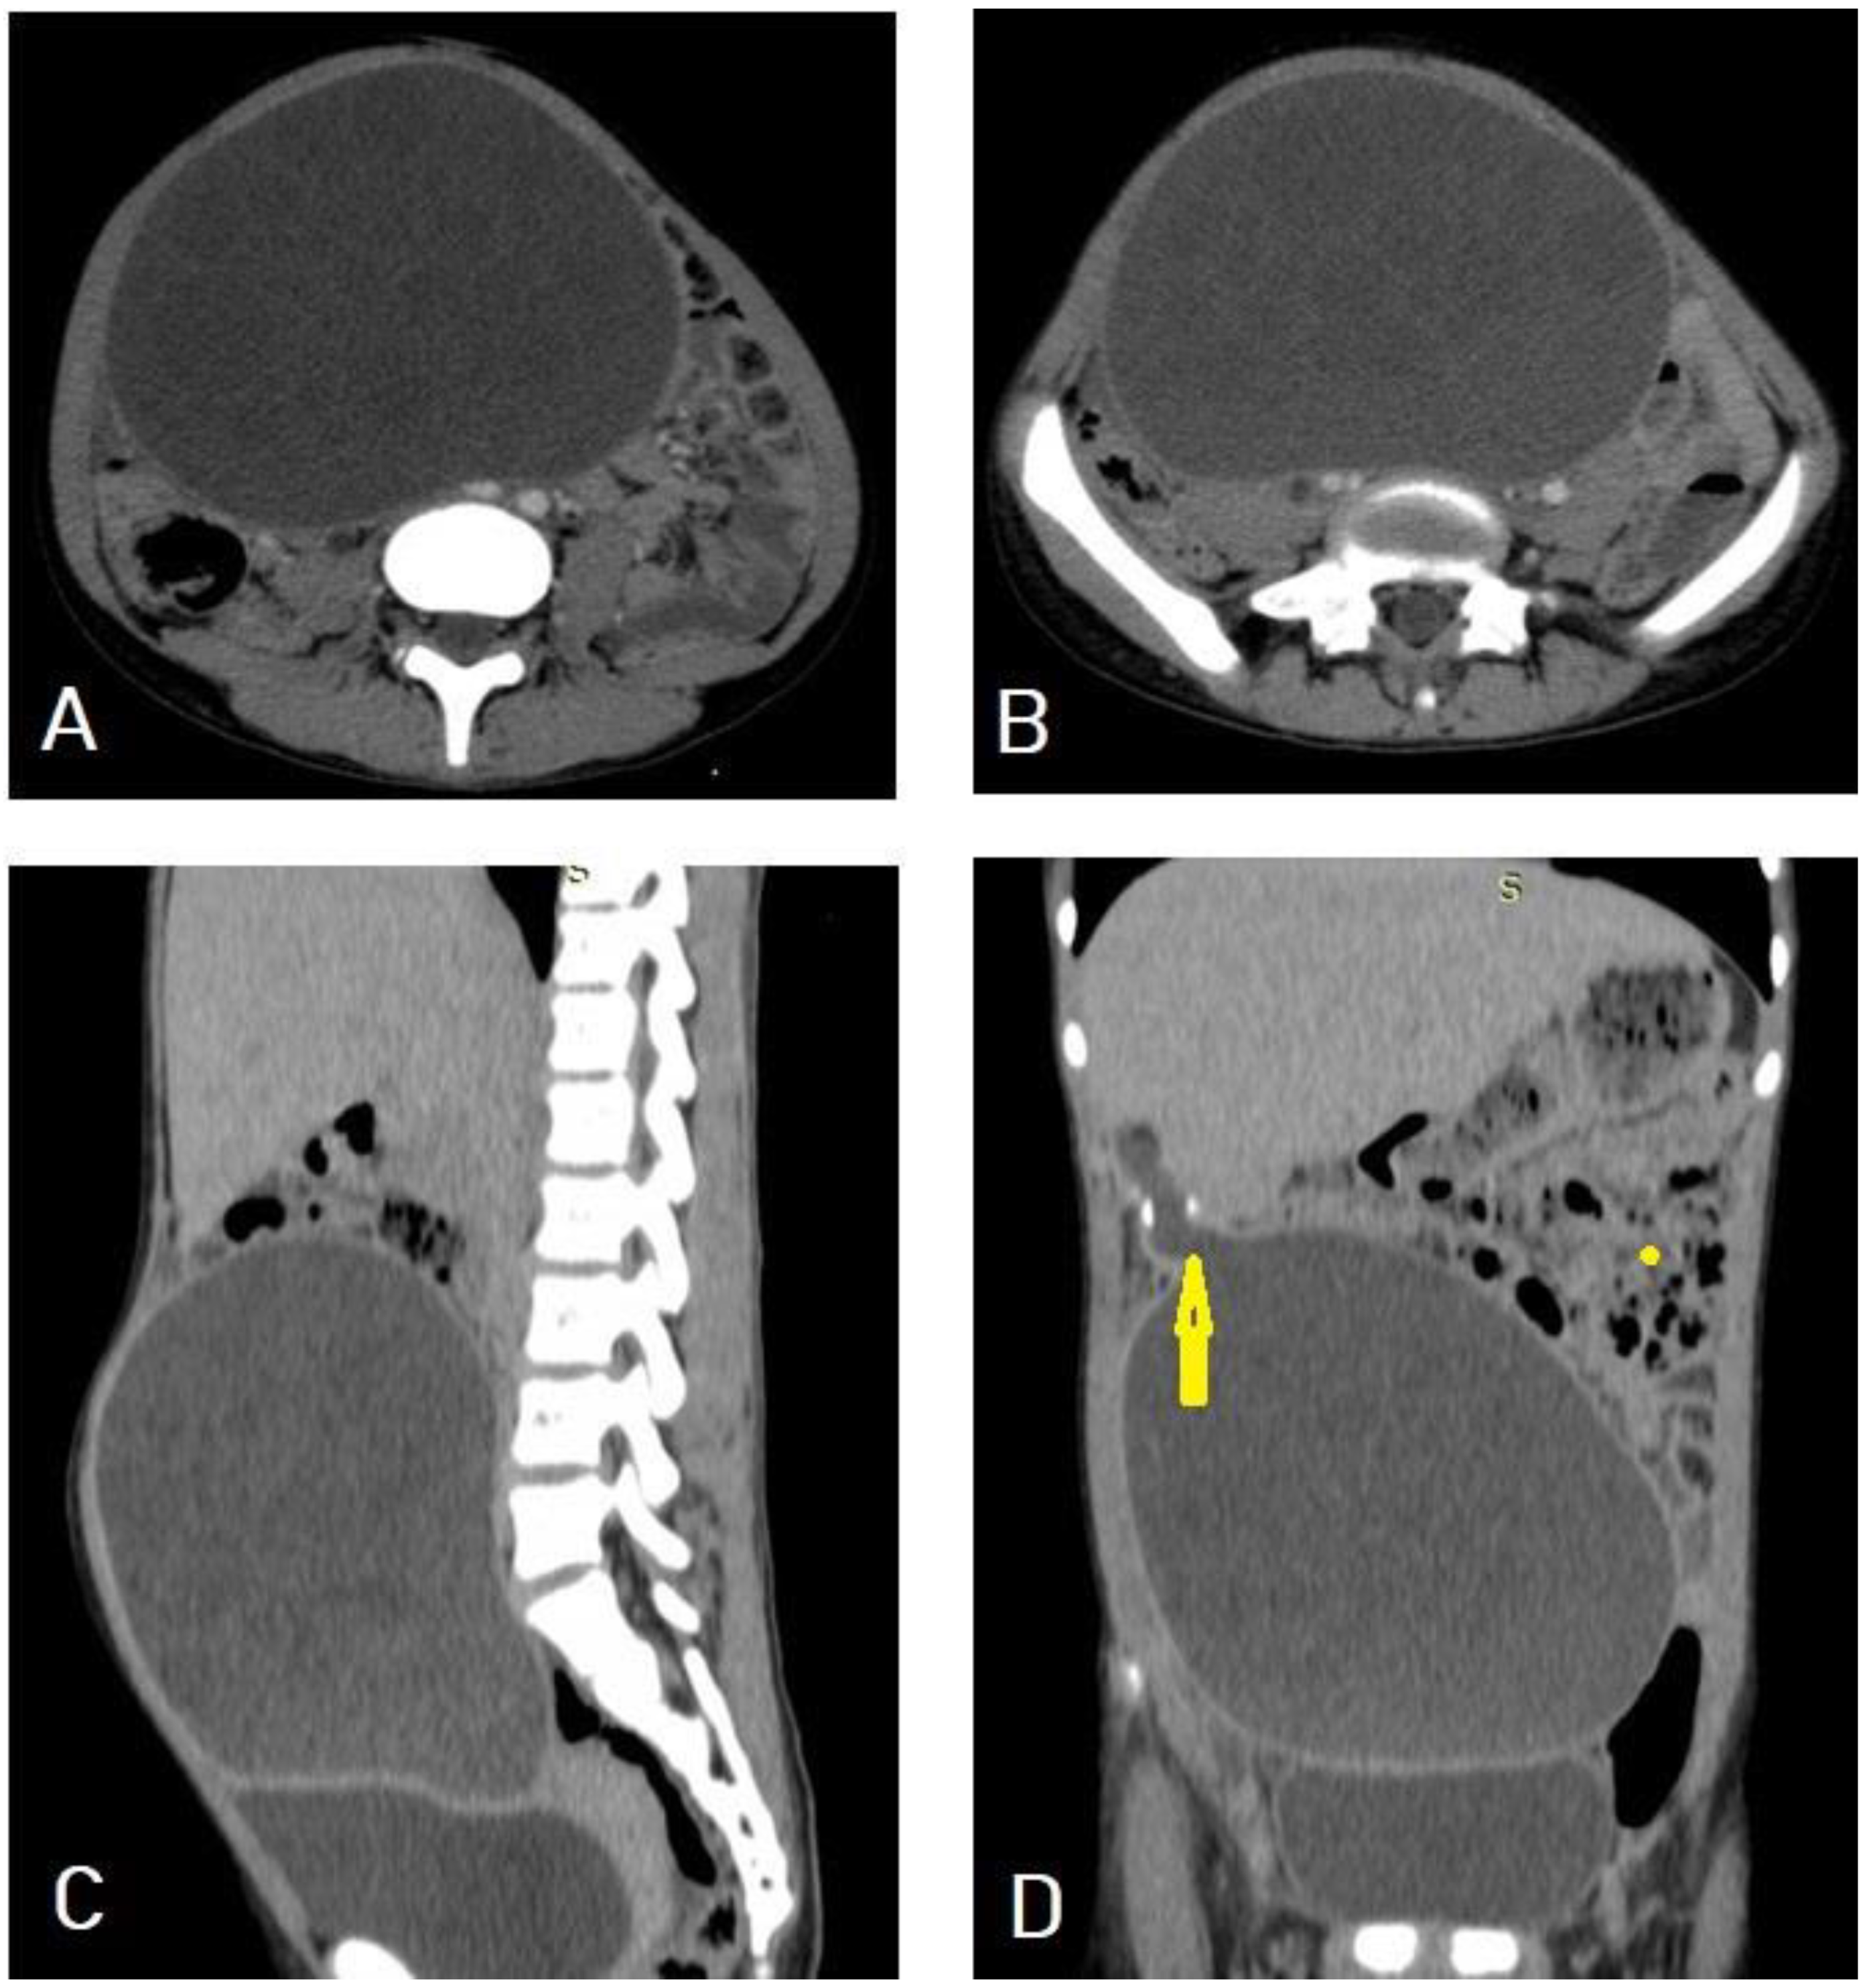

5.3. Hydatid Cysts of the Spleen